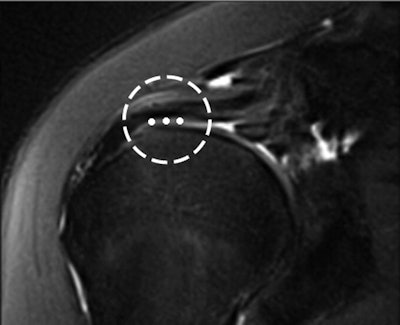

The rotator cable was visualized in 74% of the MRI studies on both coronal and sagittal oblique sequences by both readers. The mean width of the cable was 1.24 ± 0.31 cm and the mean thickness was 0.19 ± 0.05 cm.

The mean cable thickness in this study was smaller than the 0.47 cm reported in previous research, the authors noted.

"This was most likely because the original measurements [in the previous study] included the adjacent joint capsule and rotator cuff tendon fibers in addition to the cable," Gyftopoulos and colleagues explained.